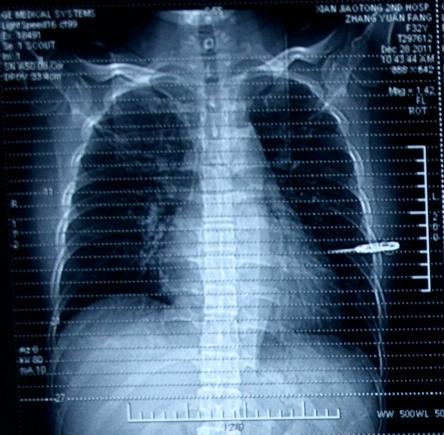

入院时的胸部X线片:见图1

图1